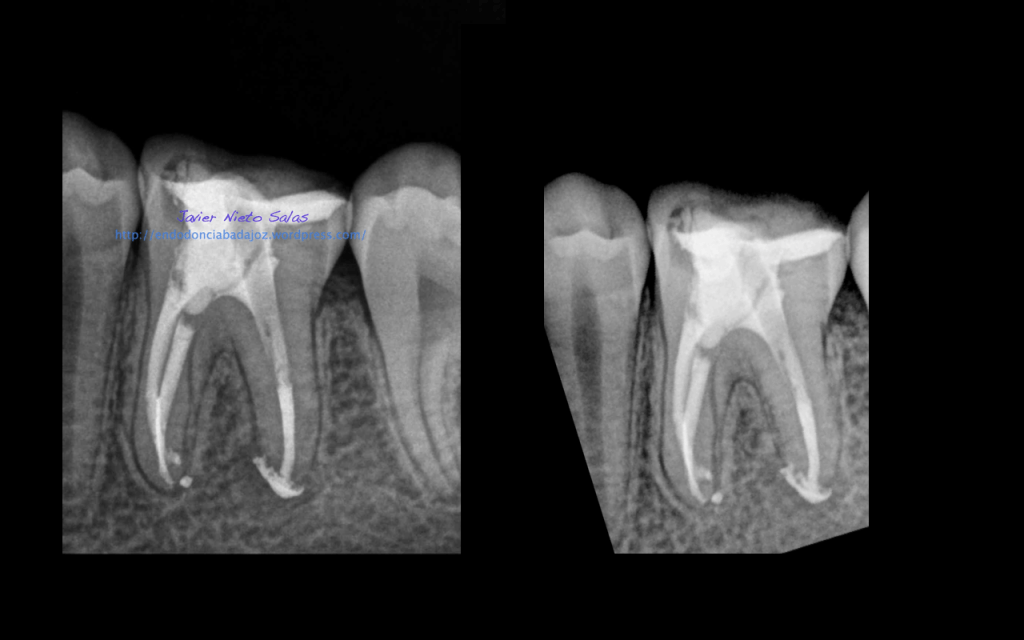

Llamamos a la paciente a revisión a los 10 meses:

También se llamo a revisión a los 10 meses.

Son ese tipo de casos que nos aportan mucha confianza en nuestro trabajo, el cual defendemos «a capa y espada». Esta claro que no todos los casos los resolvemos de la misma manera, hay varios factores que nos determinaran como realizaremos el tratamiento.

Con respecto a tu pregunta sobre las dos últimas Rx, que son la revisión de las anteriores, de una periodontitis apical crónica de un 4.6, si puedes observar en la radiografía distalizada final, existe un istmo entre ambos conductos, y puede ser que exista un conducto lateral, pero como ya sabemos, existe una gran complejidad anatómica del sistema de conductos. El blog de Ronal Ordinola, es fantástico, y puedes ver esas anatomías en las que piensas en que la endodoncia es un verdadero RETO.